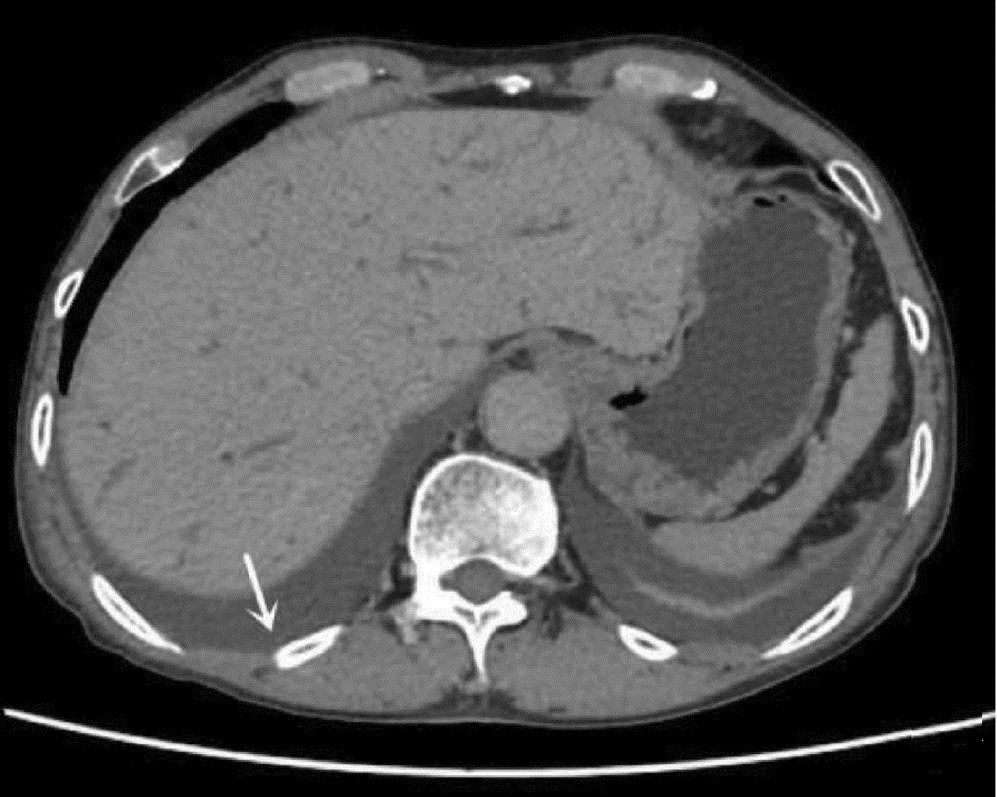

Hepatitis B cirrhosis with hepatic paragonimiasis misdiagnosed as primary liver cancer: A case report

Shenfeng HUANG, Jiajun LIN, Yang TAN, Zhifang CAI

2022, 38(6): 1367-1369. DOI: 10.3969/j.issn.1001-5256.2022.06.028

Abstract(985) HTML (273) PDF (2412KB)(52)

Abstract: